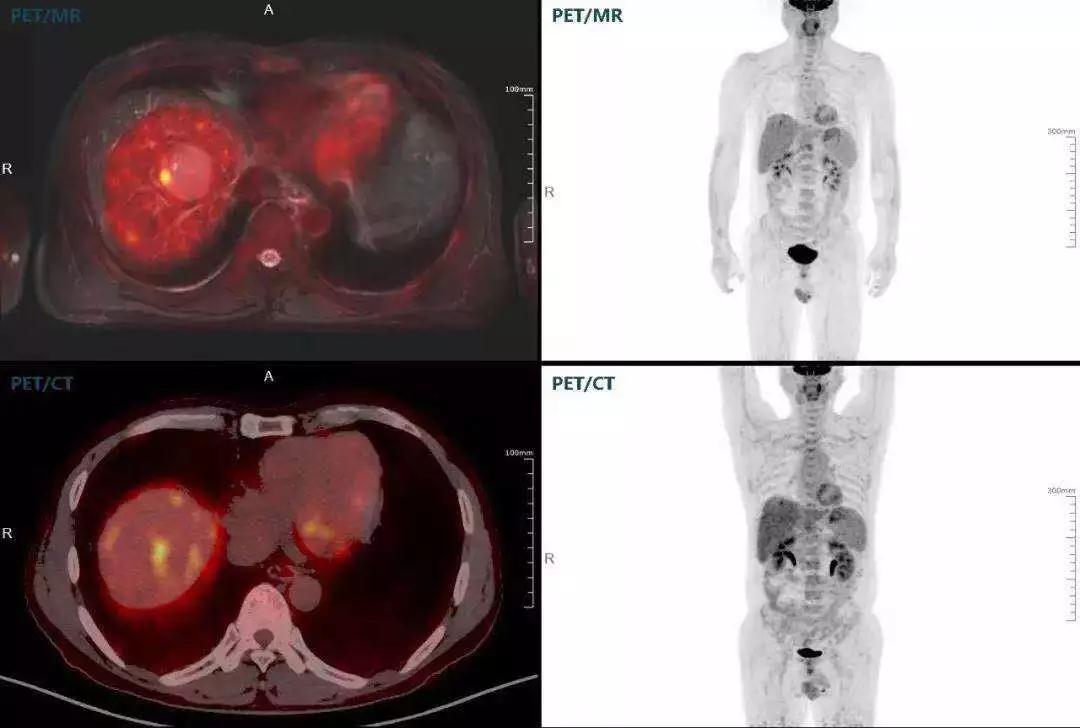

肝癌

聯(lián)影“時(shí)空一體”超清TOF PET/MR搭載的壓縮感知技術(shù),能夠同時(shí)實(shí)現(xiàn)16期成像,精準(zhǔn)捕獲肝臟動(dòng)態(tài)影像的每一瞬間,同時(shí)兼顧早期與晚期等全部期相的完整病灶信息,實(shí)時(shí)、全方位鎖定病灶。同時(shí),基于其2.8mm超高分辨率,能夠精細(xì)呈現(xiàn)腫瘤邊界信息,捕捉局部微小病灶與遠(yuǎn)端轉(zhuǎn)移灶,助力醫(yī)生精準(zhǔn)診斷。

(對(duì)于同一例肝臟惡性腫瘤,PET-CT與PET/MR成像對(duì)比??梢钥吹?,聯(lián)影PET/MR圖像對(duì)腫瘤邊界和FDG高濃聚區(qū)域清晰顯示。)